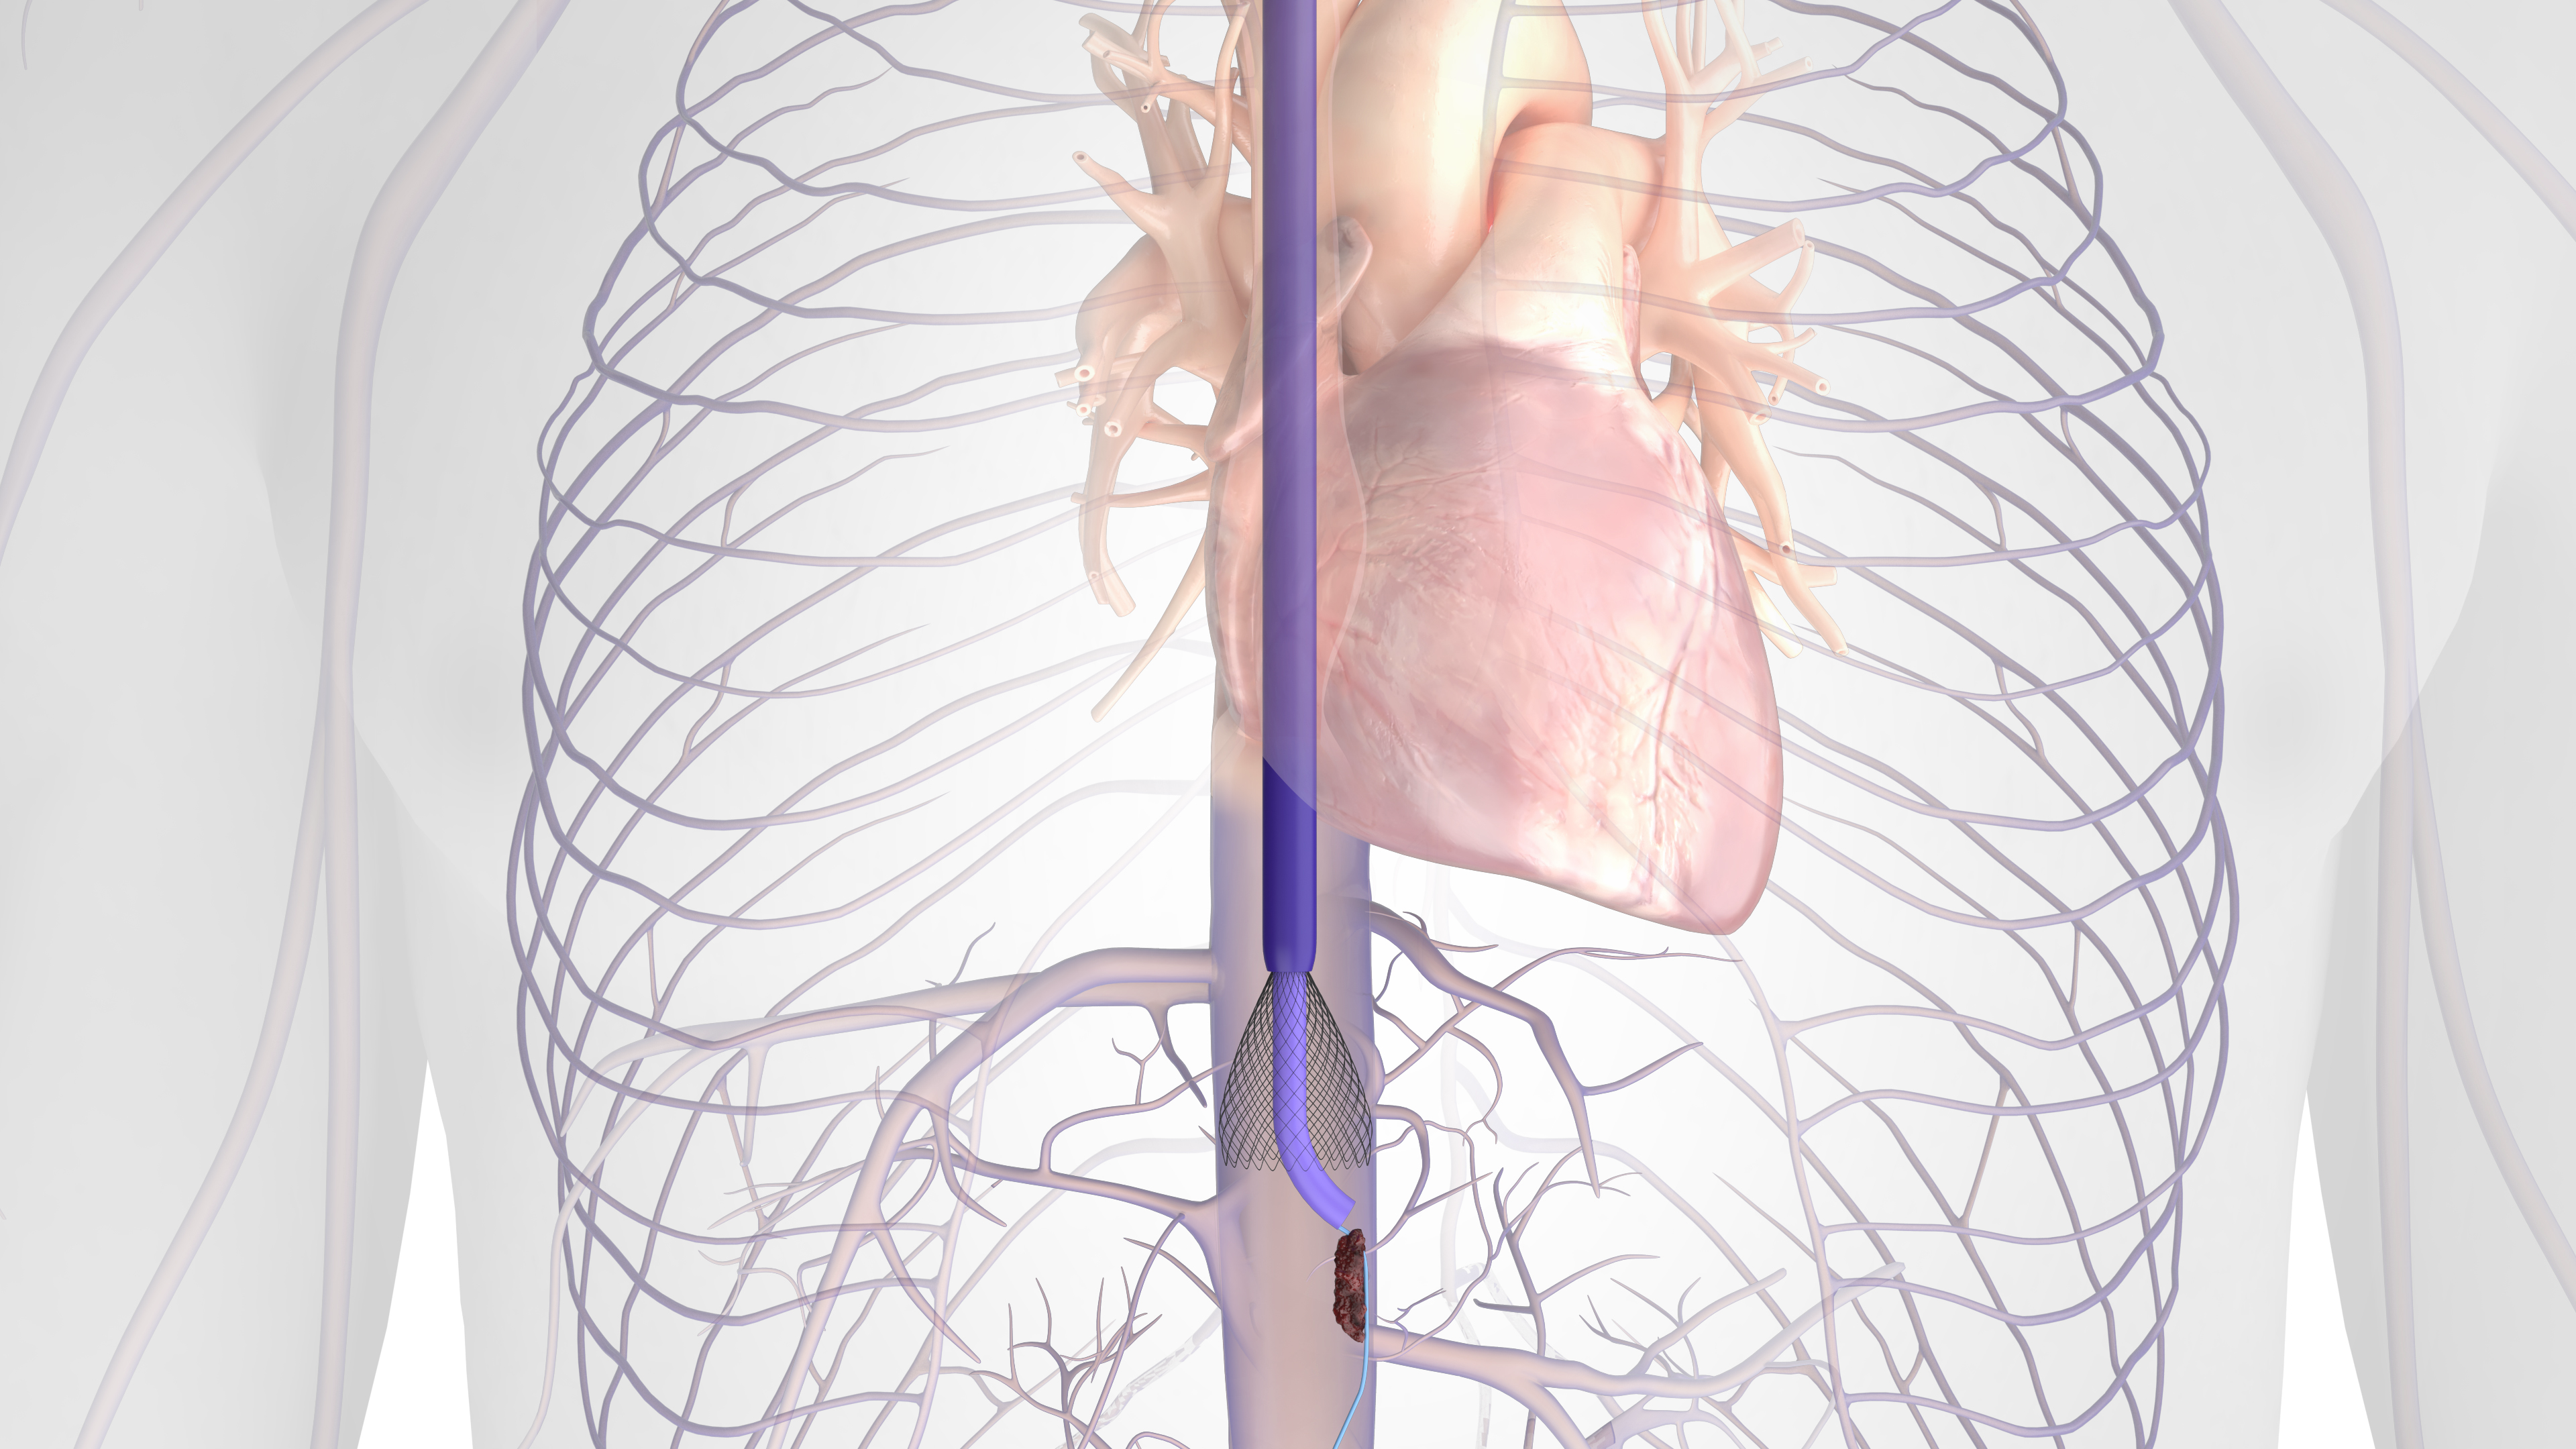

Dr. Shaikh: One of the main advantages of the Protrieve sheath (20 F) is the nitinol mesh funnel at the distal end of the device (Figure 1). The sheath is introduced from an IJ access and advanced into the IVC, and the 33.5-mm nitinol mesh funnel is deployed using the side actuators. The funnel gains full wall apposition in the caval region, which ultimately means that I can take on challenging cases knowing that the device is capable of trapping emboli. The sheath also has a large-bore side port for aspiration of residual thrombus trapped in the funnel, which is very useful in these cases.

The sheath was designed to simplify complex DVT and IVC procedures, and it has done that in my practice for sure. The nitinol mesh funnel is intended for vessels up to 30 mm (17–30 mm treatment range), which is a perfect size, even for a dilated IVC. The actuators on the side work smoothly to deploy and then recapture the funnel. And, when the Protrieve sheath and funnel are deployed, it becomes possible to use the FlowTriever toolkit (Figure 2) and ClotTriever catheters from an IJ approach, which was not the case previously.